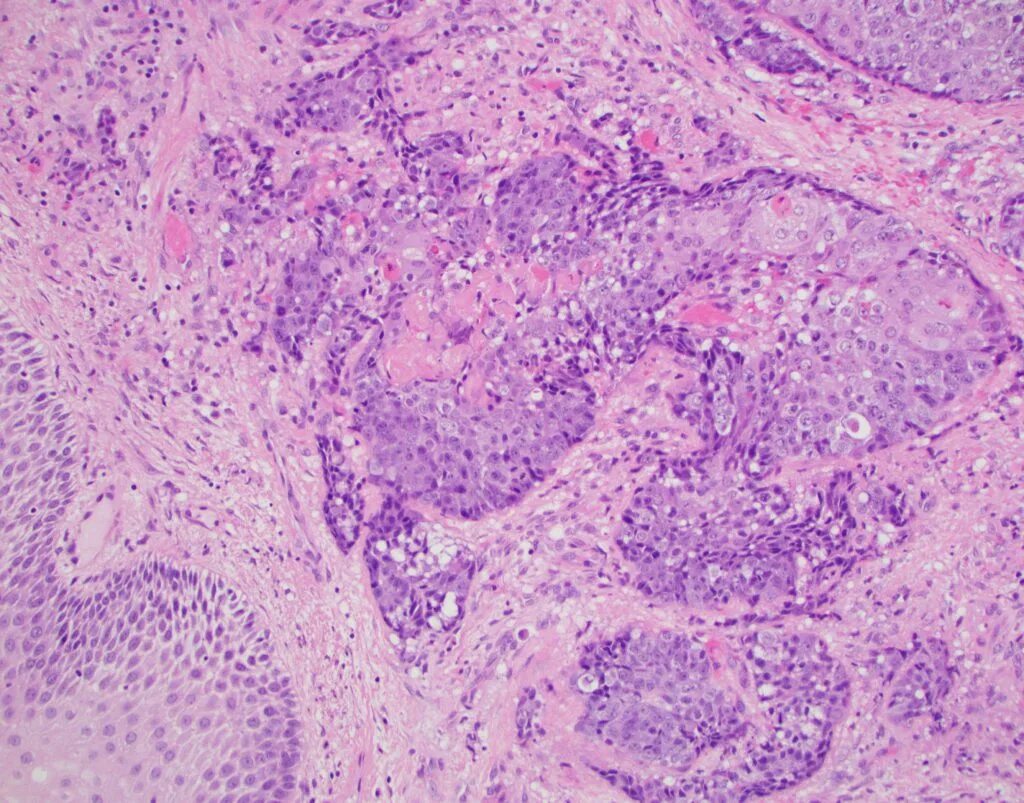

Плоскоклеточная опухоль